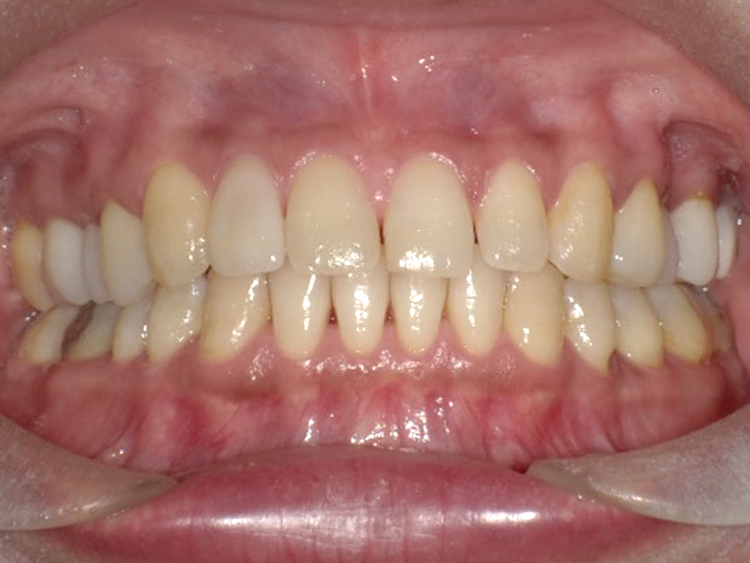

症例6

Before

After

| 主訴 | 噛み合わせが気になる |

|---|---|

| 年齢 | --- |

| 治療 期間 |

約2年11ヶ月 |

| 治療 内容 |

インビザラインコンプリヘンシブ 右上6番・左上6番ALLセラミッククラウン |

| 治療費 | ¥1,116,000(税込)/調整料含む |

| 治療のリスク | 歯を動かすことで、歯茎が下がるリスクある。 矯正終了後は、リテーナーを使用し、後戻りを防ぐ必要がある。 |